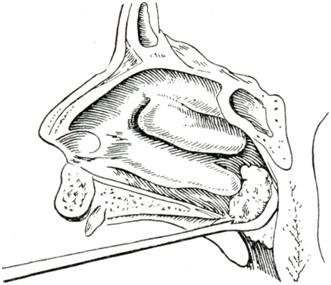

Рис. 5. | ||

Детям старшего возраста смазывают наиболее чувствительные боковые стенки носоглотки через нос и рот 1—2% раствором дикаина или 5% раствором кокаина с адреналином (некоторые авторы применяют вместо смазывания пульверизацию ротоглотки теми же растворами). Операцию лучше производить утром натощак. Для операции чаще всего пользуются кольцевидными ножами — аденотомами Бекманна (смотри Оториноларингологический инструментарий), которые бывают пяти размеров соответственно величине носоглотки. Некоторые врачи предпочитают для удаления аденоидов носоглоточные щипцы Штейна, Денкера или аденотомы с гильотиной типа Шитце. Инструменты для удаления аденоидов выбирают, исходя из особенностей формы носоглотки и места расположения аденоидов у данного больного.

При операции для лучшей фиксации ребенка сажают на колени помощника, который зажимает между коленями ноги больного, лишая его возможности опираться о пол; одной рукой он удерживает голову, а другой —плотно захватывает руки больного. Маленьких детей лучше заворачивать в простыню. Шпателем отдавливают язык книзу и вводят за мягкое небо аденотом, устанавливают его строго по средней линии, продвигают кверху кпереди, касаясь заднего края носовой перегородки, далее прижимают вверху к своду носоглотки. Затем быстрыми движениями спереди назад по куполу и далее сверху вниз по задней стенке носоглотки срезают аденоиды (рис. 5). Если остаются обрывки ткани, свисающие в глотку, то их скусывают конхотомом или отрезают изогнутыми ножницами. Удаление аденоидов обычно сопровождается кровотечением, которое быстро останавливается. После очистки полости носа попеременным отсмаркиванием (или же потягиванием воздуха из носа к глотке) вдувают через нос дезинфицирующий порошок (например, смесь сульфаниламидов). Если операция была произведена в амбулатории, то ребенка задерживают на 1,5—2 часа, после чего, убедившись в отсутствии кровотечения, отпускают домой. В течение первых 2—3 дней после операции рекомендуется постельный режим и еще 2—3 дня комнатный. Температура пищи должна быть в пределах 18—20°. Уборка помещения, где находится больной, производится влажным способом.